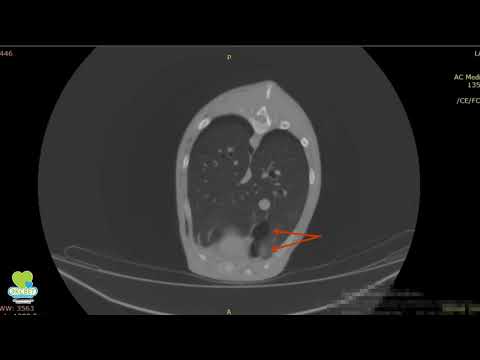

Буллы на кт

Буллы на кт 105 фото